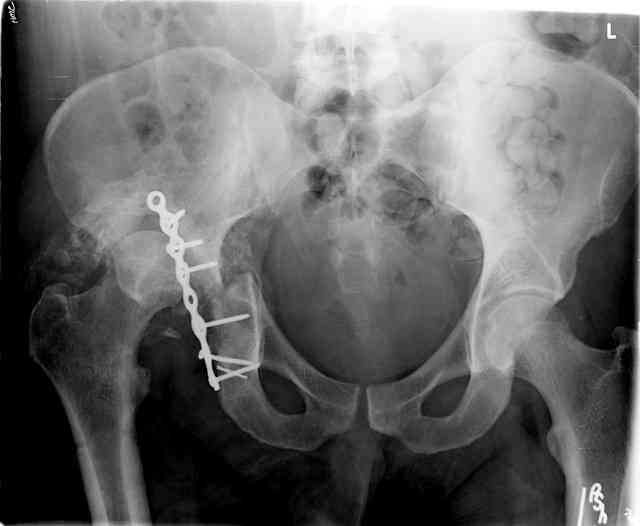

I'll include a few images of a similar injury in a similarly large male patient. This patient "showed up" in our ER c/o hip pain 2 months after being treated in the lateral position, without a quality reduction, without an anterior column transverse supporting implant, with an unbalanced plate applied too medially, with insufficient caudal segment fixation...it took over 8 hours and a 3+ l blood loss to debride the callus from front then

back, excise the HO, release his sciatic nerve, reduce the head-transverse-wall, and fix it...and now it's a staging procedure.